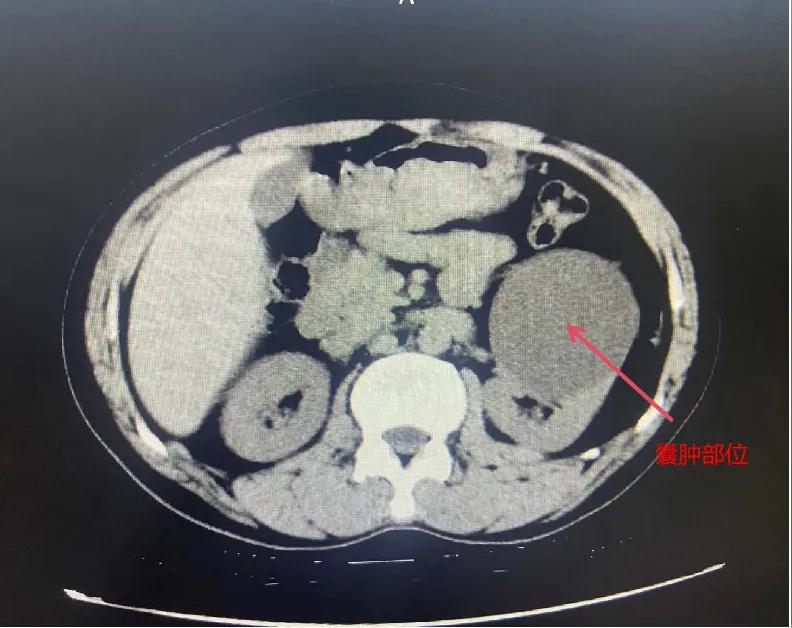

漯河市骨科醫(yī)院泌尿外科開展后腹腔鏡下腎囊腫去頂減壓術(shù)

近日,漯河市骨科醫(yī)院(漯河醫(yī)專二附院、漯河市立醫(yī)院)連續(xù)收治2例腎囊腫患者。泌尿外科主任閆衛(wèi)甫和副主任醫(yī)師王金柱等醫(yī)師團隊經(jīng)討論研究后,決定為患者采取后腹腔鏡下腎囊腫去頂減壓術(shù),經(jīng)過手術(shù)室、麻醉科等科室大力配合成功完成手術(shù)。

閆衛(wèi)甫表示,后腹腔鏡技術(shù)是一種微創(chuàng)外科手術(shù)方法,它通過在后腹腔(即腹膜后的空間)建立一個手術(shù)空間,利用腹腔鏡器械進(jìn)行手術(shù)操作。這種技術(shù)特別適用于泌尿系統(tǒng)等后腹腔臟器的手術(shù)。與傳統(tǒng)手術(shù)相比具有創(chuàng)傷小、恢復(fù)快、并發(fā)癥少、視野清晰等優(yōu)點。與前腹腔鏡相比則具有對腹腔臟器干擾較少的優(yōu)點。目前,后腹腔鏡手術(shù)主要用于腎囊腫去頂減壓術(shù)、腎上腺腫瘤切除、早期腎癌根治術(shù)、腎腫瘤剜除術(shù)等。

腎囊腫是一種常見的腎臟良性疾病,其發(fā)病率逐年增加。近年來隨著腹腔鏡技術(shù)的迅速發(fā)展,后腹腔鏡下腎囊腫去頂減壓術(shù)成為治療腎囊腫的主要方法。該手術(shù)具有創(chuàng)傷小,手術(shù)時間短,術(shù)中出血少,術(shù)后康復(fù)快,出院時間短等優(yōu)點,并且術(shù)后復(fù)發(fā)率低,被認(rèn)為是治療腎囊腫的理想術(shù)式。(盧 闖 聶方方 劉 旭 袁錦鈺)